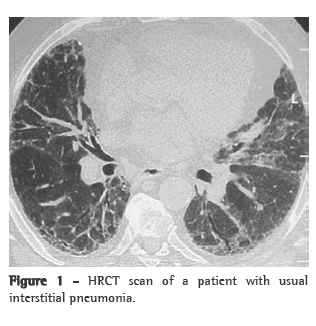

Another recommendation is to obtain a sample of the area of transition between the clearly diseased region seen on HRCT scans and the apparently normal region.(24) An excellent evaluation of the entire lung parenchyma is possible using HRCT, which is routine practice in the initial evaluation of interstitial lung diseases.(25) Currently, HRCT is used as a routine test in the preoperative period of any surgical lung biopsy (Figure 1). With reasonable accuracy, HRCT allows the selection of ideal sites at distinct stages of the disease in the lung parenchyma to be biopsied.

For most thoracic surgeons, the middle lobe and the lingular segments are anatomically easy to resect, either by mini-thoracotomy or by video-assisted thoracoscopy. In the other lung segments, the collection of samples involving the central and peripheral regions is made difficult by the need to cut an appropriately sized wedge in the parenchyma. In order to obtain a standard sample of this type, the wedge should reach a depth of more than 2 cm, the mean thickness of the peripheral lung region (Figure 2).